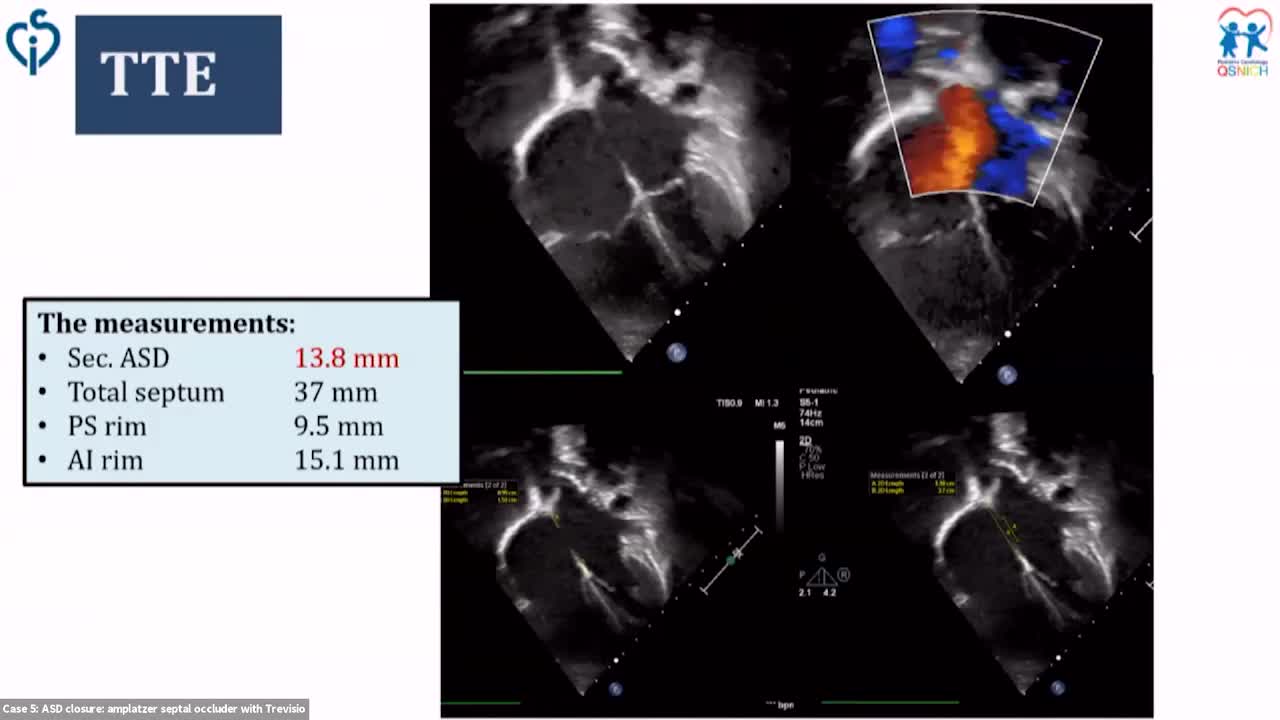

Cathlab Live Cases